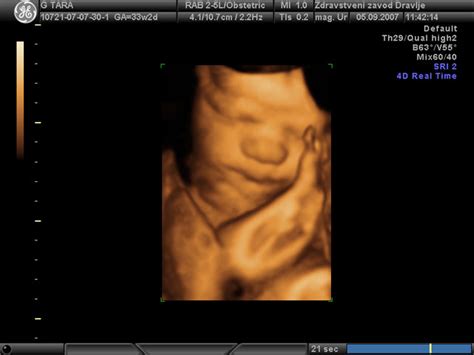

- Prva ultrazvočna preiskava: Opravi se med 8. in 12. tednom nosečnosti z namenom izključitve izvenmaternične nosečnosti, izključitve ali potrditve zgodnje nosečnosti.

- Druga ultrazvočna preiskava: Opravi se okrog 20. tedna nosečnosti. To je rutinski ultrazvočni pregled za potrditev ali določitev razvoja ploda.

- Dodatni ultrazvočni pregled: Pri obremenilni anamnezi ali kliničnem izvidu se opravi ultrazvočni pregled v 30. do 32. tednu nosečnosti, ki je del kurativne obravnave. Enako velja za ultrazvočno ugotavljanje lege posteljice.